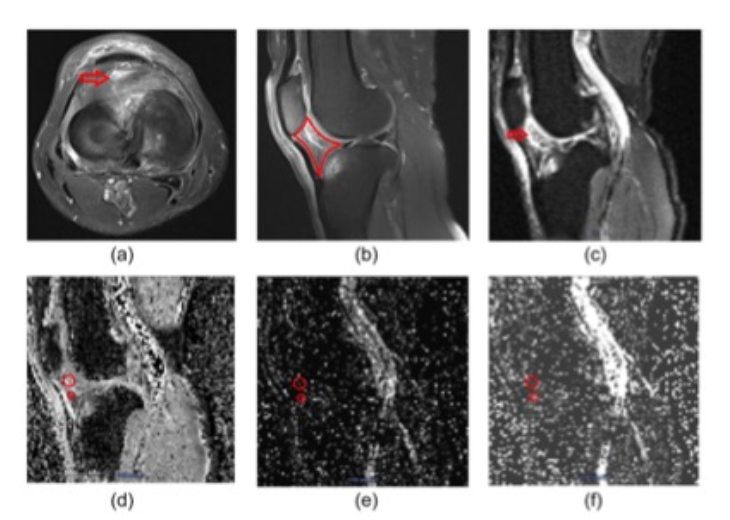

图 一名63岁的男性患者,患有KOA,HLG=3,WOMAC-疼痛评分=38。在横断面和矢状面PdWI上,IPFP的前上方有明显的异常信号强度变化(a和b)。分别在PdWI高信号区和邻近的正常信号区画出两个ROI。在IPFP中手动将ROI放在具有较好信噪比的b=0 DWI图上(3c),然后将ROI自动复制到D、D*和f图上(3df)。PdWI-HR和相邻的PdWI-NSIR的D、D*和f值分别为1.93 £ 103 mm2/s vs. 0.92 £ 103 mm2/s,26.33 £ 103 mm2/s vs. 20.09 £ 103 mm2/s,以及0.34 vs. 0.29